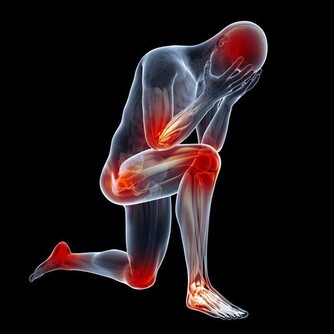

痛風症狀

痛風石中老年人比較常見的疾病之一,男性患者比較多,往往夜間突然發病,局部關節紅腫、疼痛劇烈,皮膚會呈青紫色、發亮,有明顯的壓痛感以及局部隆起現象,有時關節還會有活動障礙現象的發生。